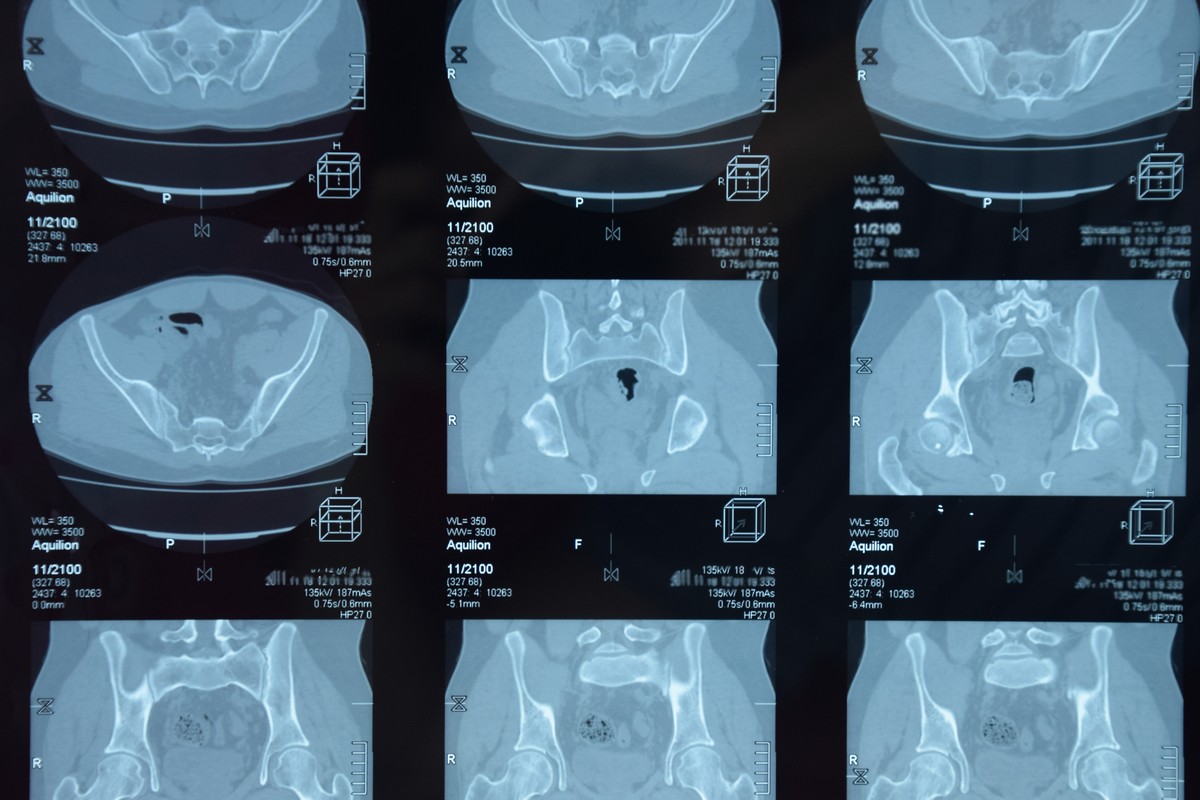

На МРТ ангиографии четко визуализируются сосуды, строение, состояние клапанов, наличие внутрисосудистых и внешних новообразований, влияющих на кровоток.

На МР-венографии хорошо визуализируются аномальные мембраны, сужение (стеноз) или перекрытие (окклюзия) венозного сосуда, характер кровотока, кровоснабжение внутренних органов и ног. На основании данных исследования врач может поставить диагноз синдрома нижней полой вены, тромбофлебит, обнаружить на ранней стадии опухоли и другие образования.

В клинике «РЭМСИ Диагностика» МРТ-венографию проводят на оборудовании американского производства Optima-360 от General Electric. Аппарат работает на мощности 1.5 Тл. Во время обследования проводится сканирование, включающее тысячи снимков. С помощью программного обеспечения из них получается полномасштабное и изображение. Врач может поворачивать его в разных плоскостях, увеличивать необходимые участки в несколько десятков раз, создать 3D модель нижней полой вены. Это дает возможность получить очень точные результаты и поставить точный диагноз с первого раза.